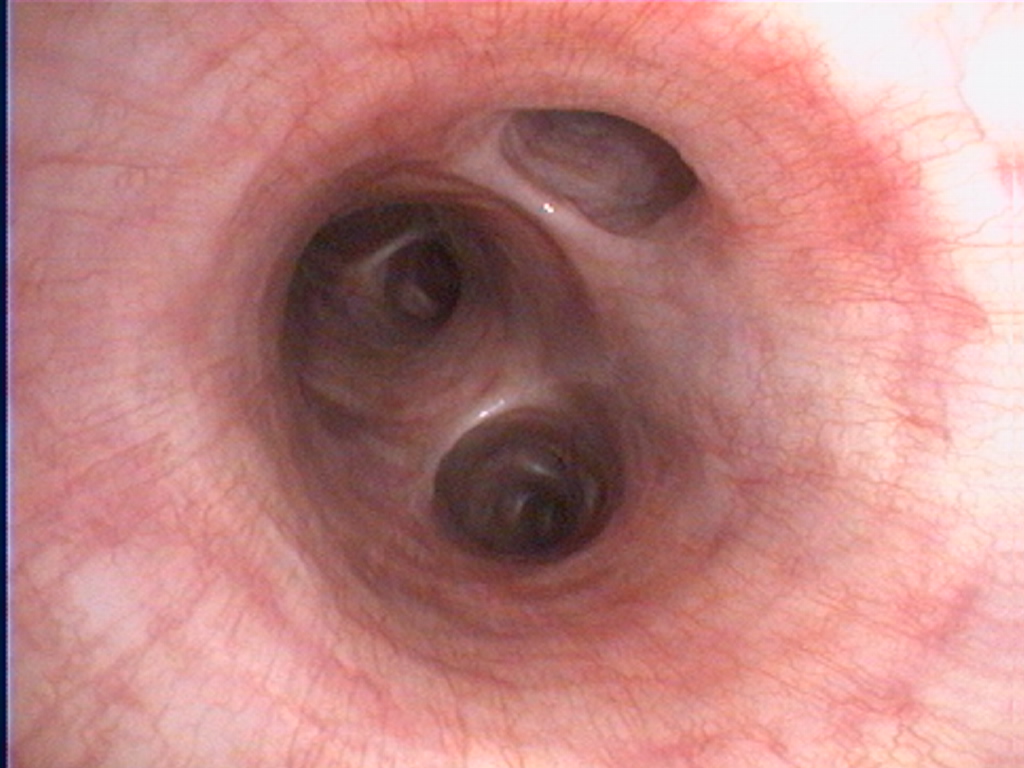

Endoscopie des voies respiratoires sur un chien.

De gauche à droite : larynx, trachée avec la carène, bronches.